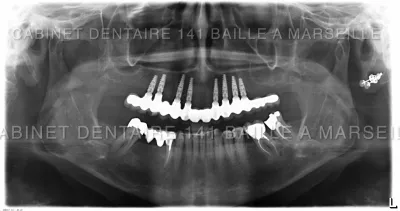

Chirurgie implantaire guidée par spécialiste marseille

Chirugie Guidée en Implantologie dentaire Une avancée technique .Docteur didier Tourrolier

La chirurgie implantaire guidée est une approche innovante dans le domaine de l'implantologie dentaire qui utilise des technologies numériques de pointe pour améliorer la précision et la sécurité du placement des implants. Con...

Implant Bouche Complete Marseille Prix-Cabinet d'implantologie 141 Baille.

Dans certains cas il est possible de remplacer toutes les dents d'une arcade dentaire par des implants dans la meme séance avec une mise en place de prothèse dentaire fixée sur les implants le jour meme .Explications,description de la technique ,Coût du traitement